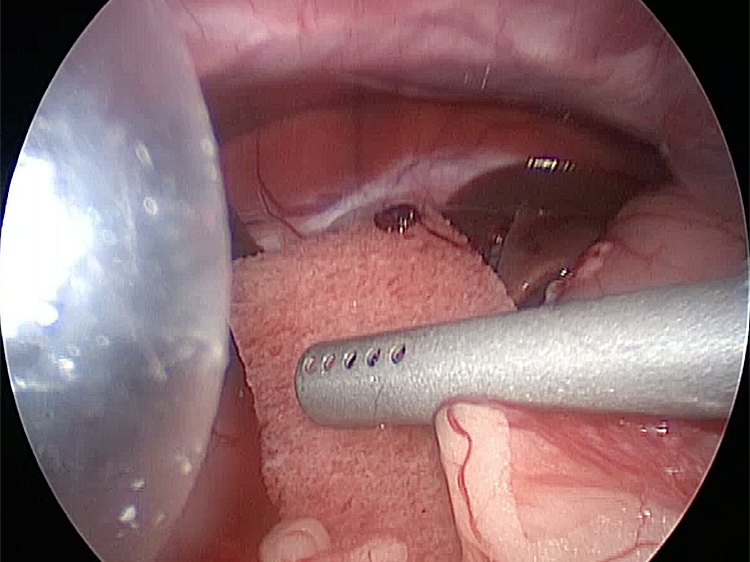

胆嚢の通路がちゃんと開通しているのか調べるために造影検査をしています。 この処置をすることで洗浄の効果と詰まりを確認することができます。

総胆洗浄をして詰まりがないかまずは確認します。

きれいに開通していました。鉗子が大きく感じますが体が小さいので大きく見えます。

詰まりがないかを透視で確認しています。